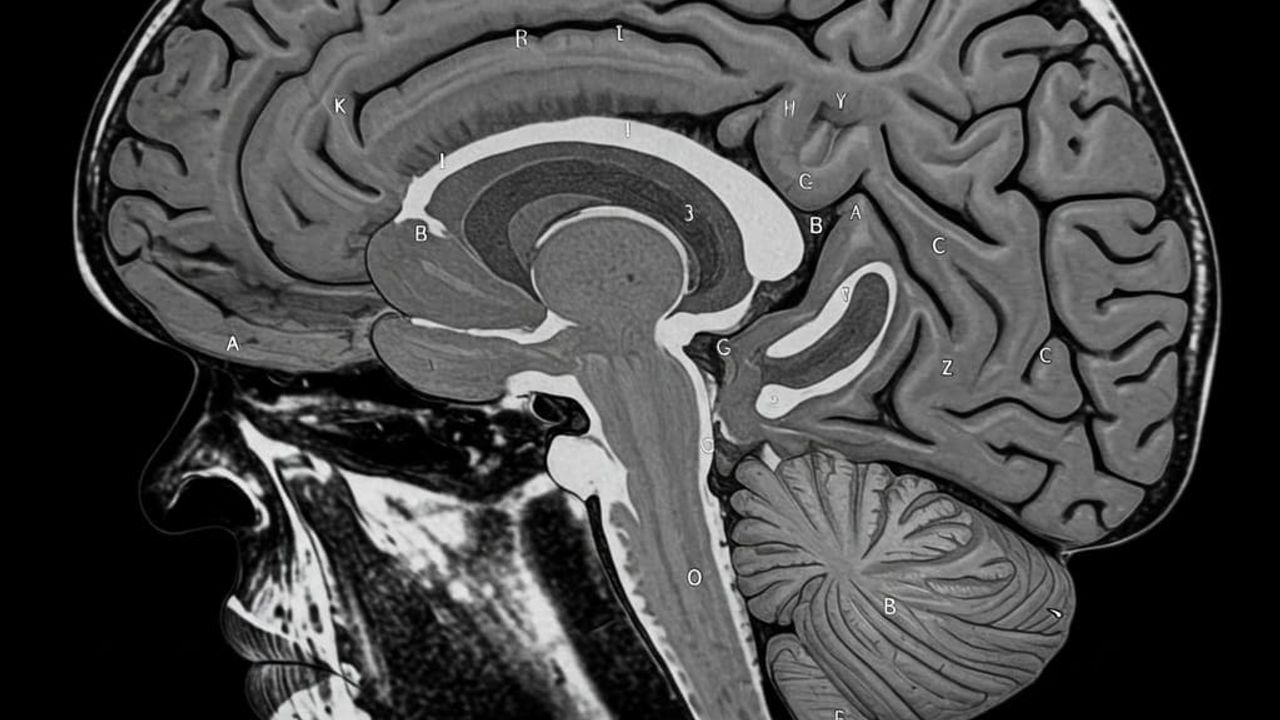

Beyindeki Plastik Oranı 8 Yılda Yüzde 50 Arttı

ABD'de gerçekleştirilen ve sonuçları saygın tıp dergisi Nature Medicine'de yayınlanan bir araştırma, insan beynindeki mikroplastik birikiminin endişe verici boyutlara ulaştığını ortaya koydu. Çalışmada incelenen kadavra beyinlerinde, sadece sekiz yıl içinde mikroplastik miktarının yaklaşık yüzde 50 oranında arttığı belirlendi.

Araştırmada, otuz farklı kadavranın beyin, karaciğer ve böbrek dokuları detaylı bir şekilde analiz edildi. Elde edilen bulgular, beyindeki plastik yoğunluğunun gram doku başına yaklaşık 4000 mikrogram olduğunu gösterdi. Bu konsantrasyonun, karaciğer ve böbrekte tespit edilen miktarın yaklaşık on katı daha fazla olduğu saptandı.

Araştırmalar, beyinde ölçülen mikroplastik miktarının beynin ön bölümünde yaklaşık 2 grama ulaştığını, bu miktarın ortalama bir plastik poşetteki plastik miktarına eşdeğer olduğunu gösteriyor. Tespit edilen mikroplastiklerin çaplarının ise 500 mikrondan 1 nanometreye kadar değiştiği, yani bir saç telinden bile çok daha ince olduğu belirtildi.